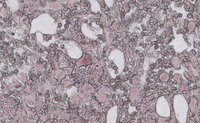

Figure 2: Images of bone marrow core biopsy in CML–accelerated phase

Low power image demonstrating markedly hypercellular marrow with significantly increased numbers of megakaryocytes visualized at higher power.  The image at the bottom depicts numerous megakaryocytes that comprise an admixture of dwarf forms with hypolobated nuclei (typical in CML) as well as forms comprising micromegakaryocytes with dysplastic features.  The background comprised and equal admixture of maturing myeloid and erythroid precursors without the typical myelocyte bulge seen in chronic myeloid leukemia, chronic phase.